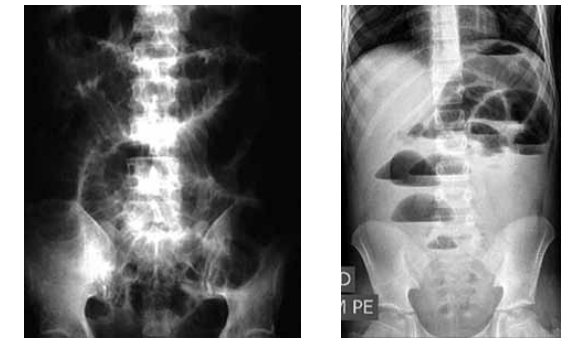

Homem de 45 anos procurou pronto-atendimento com história de náuseas, vômitos e distensão abdominal há 2 dias. Não elimina flatos ou fezes desde então. Foi submetido a uma laparotomia exploradora aos 40 anos por ferimento abdominal por arma de fogo (FAF). Foi uma operação extensa, segundo relato do paciente, em que foi removido mais de 1 metro de intestino delgado. Ao exame físico: em regular estado geral, um pouco desidratado, PA: 110 x 80 mmHg, FC: 85 bpm, RHA aumentados, abdome globoso, timpânico, globalmente doloroso, sem sinais de peritonite. Apresenta RX abdome (posição supina e ortostática) a seguir.

Qual o diagnóstico sindrômico e etiológico mais provável e a conduta inicial mais indicada?